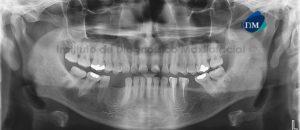

Paciente masculino, 54 años es referido al Instituto de Diagnóstico Maxilofacial para planificación de cirugía guiada con el objetivo de colocar implantes dentales en el